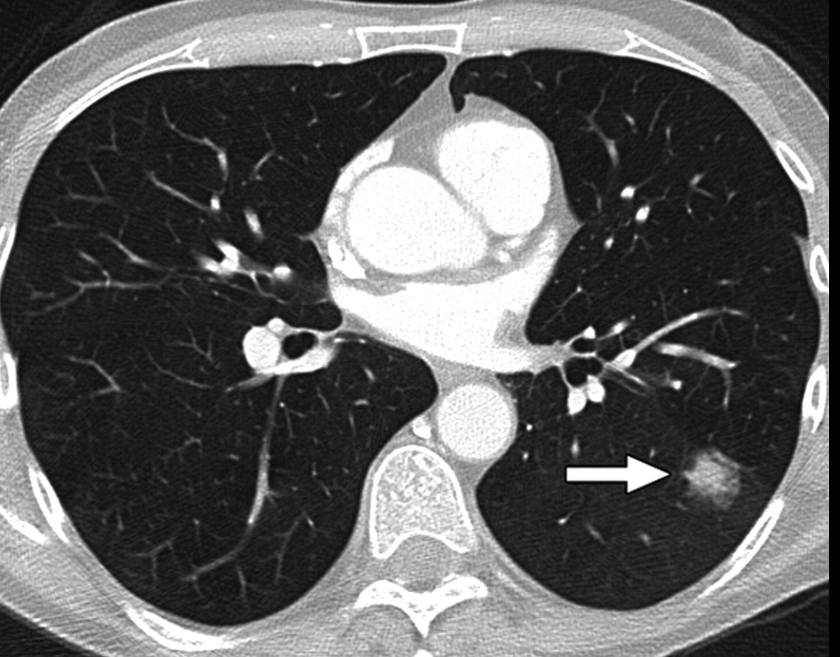

폐 편평세포암은 폐암의 한 유형으로, 주로 흡연과 관련이 있습니다. 기침이 3주 이상 지속되거나 피 섞인 가래, 숨이 차는 증상이 있으면 검사를 받아야 합니다. 흡연자는 비흡연자보다 편평세포암 발생 위험이 몇 배나 높습니다. 금연은 가장 강력한 예방책이며, 폐 건강을 지키는 가장 직접적인 방법입니다.

진단은 흉부 X선, CT, 기관지 내시경, 조직검사로 이뤄집니다. 치료는 수술, 방사선, 항암치료, 면역치료가 병합됩니다. 최근에는 맞춤형 치료제가 도입되어 생존율이 향상되고 있습니다.